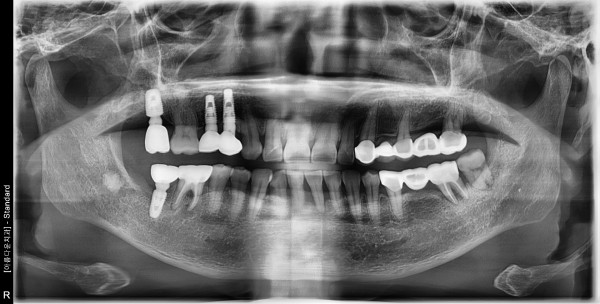

▶63세 여성환자분 / 아래 앞니 흔들림호소로 방문

아래 앞니 흔들리고 냄새가 나고 고름이나와서 내원하심.

염증으로 인하여 잇몸뼈가 많이 녹아 있는 상태 였슴.

■ 당일 발치 후 치조골이식실 시행

□ 3개월 후 임플란트 식립 후 보철물 완성

앞니 이기 때문에 심미적인것을 놓칠수 없는 점이 있어서

기공실장님과 협조하여 환자분이 만족하는 보철물 완성하여

매우 만족해 하셨습니다.!!